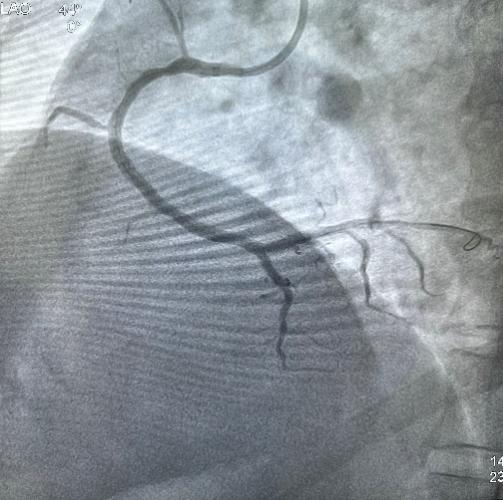

5月31日经过充分的术前准备,雷新军教授带领景林德博士和李瑞峰医生按照预定方案为患者实施了手术。冠脉造影示:RCA 2段节段性狭窄约25%,末端狭窄约90%,为不稳定斑块,血流TIMI 3级(图2a)。决定干预右冠:6F SAL1.0指引导管到位后,先操控Sion导丝通过病变至LV末端,然后再沿导丝送入血管内超声(intravenous ultrasound,IVUS)检查,结果显示RCA 2段末狭窄最重部位血管面积为2.30 mm2,斑块负荷为85%,手术指征明确(图2b)。首先,使用NC Balloon 3.0 x 15 mm 20 atm预扩张靶病变,造影示残余狭窄约25%,再在IVUS指导下植入Xinsorb BRS 3.5 x 28 mm,随后采用NC Balloon 3.5 x 9 mm 16atm逐段后扩张,造影显示支架充分膨胀,血流TIMI 3级(图2c-g)。最后,进一步使用IVUS评估手术情况,结果显示:支架充分膨胀,贴壁良好,支架远近端未见夹层,血管面积为8.01 mm2,手术效果非常满意(图2h)。术中患者无特殊不适,术后病人安返病房。

图2 经皮冠脉介入治疗